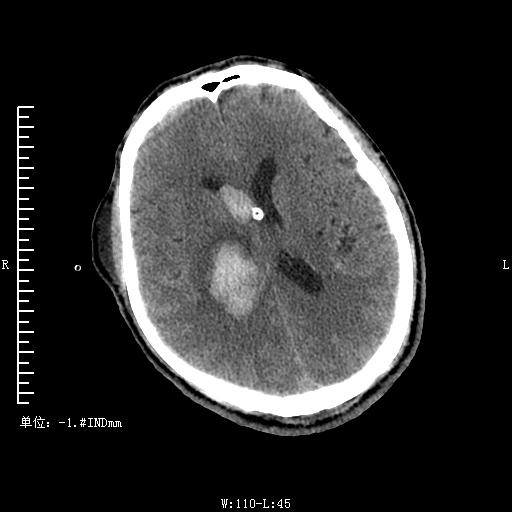

脑出血破入脑室穿刺术

患者因"发现倒在地上伴呕吐2小时。"门诊入院于内科经内科入院后经于患者家属沟通后急诊全麻下行侧脑室穿刺引流术,术后转入重症监护治疗,术后患者意识由浅昏迷转为嗜睡状,患者经治疗后清醒出院。